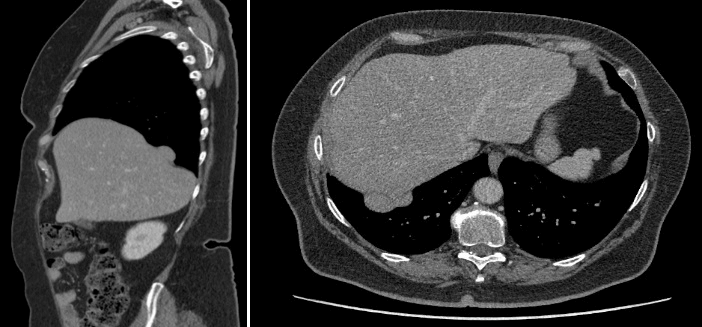

Our differential diagnoses were symptomatic gallstones, kidney stones, adhesions after surgery or recurrence of a BH. Gallstones were excluded by transabdominal ultrasound. A chest X-ray suggested a recurrence of a BH (Figure 3). Therefore, a CT scan was performed, which confirmed a small recurrence of the BH with partial herniation of the liver (Figure 4). Because of expected adhesions of the liver against the diaphragm, after the surgery performed 3 years earlier, the change in herniation of other organs was considered to be minimal. The risk of complications and chance of recurrence after a reoperation were weighted against watchful waiting and discussed with the patient. Furthermore, an opinion from surgeons not related to the case was obtained. They concluded that if the patient chooses surgery or complaints worsen, the preferred approach is a laparoscopic procedure with adhesiolysis, full mobilization of the liver, and mesh stabilization of the diaphragm. However, this kind of surgery was not preferred when complaints would be bearable. Therefore, watchful waiting was chosen. A month later, the symptoms had reduced.

Figure 3: Chest X-ray 3 years after operation. Slight elevation of the right hemidiaphragm with a round structure at the base of the right lung is shown, suggesting a possible small recurrence of a Bochdalek hernia.

Figure 4: CT scan 3 years after operation, showing small recurrence of a Bochdalek hernia with partial liver parenchyma herniation.